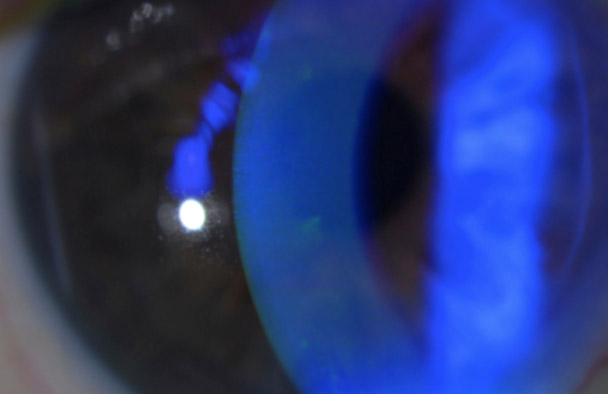

This patient presents with a foreign body sensation. Why?

In this image, there is evidence of a fluorescein dye uptake by the corneal epithelium. This patient was diagnosed with significant corneal epitheliopathy secondary to dry eye.